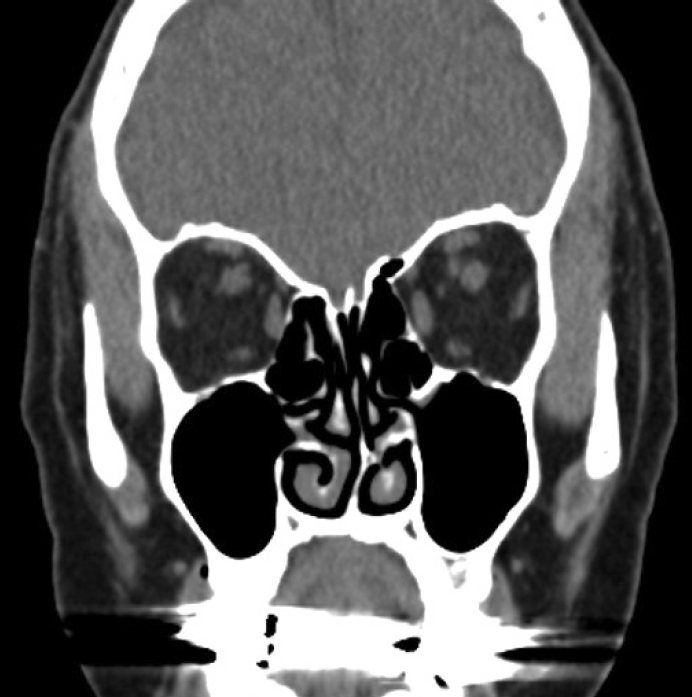

A female in their 70s presented to our clinic with left hemifacial pain, which had developed four months prior. The patient had previously received a COVID-19 nasopharyngeal swab through her left nasal cavity, and the symptoms developed immediately after the swab. The patient had no other symptoms including epistaxis after the swab except the facial pain. The patient’s medical history was not notable except for hypertension. Before visiting our outpatient clinic, the patient had undergone neurologic examinations at the neurologic department, including a brain MRI, which found no abnormal lesions in the central nervous system. The patient’s pain was restricted to the left facial area and recurred daily, lasting for several hours, and was aggravated when the patient touched their nose. A sinonasal endoscopic examination was performed by an experienced rhinologist, and a severe septal deviation to the left side was identified. The deviated portion appeared impacted on the medial mucosa of the left inferior turbinate suggesting a mucosal contact point (Fig. 1). The mucosal color of the impacted septal area was a little yellowish, differentiating it from the other parts of the septum. Paranasal (PNS) CT scans were performed to evaluate the abnormalities in the sinonasal cavity. A severely deviated bony septal abutting the medial part of the left inferior turbinate was identified in the left nasal cavity; there was no other inflammatory lesion in the sinonasal area (Fig. 2). The patient did not complain of rhinologic symptoms, such as rhinorrhea, nasal obstruction, or somatosensory symptoms. A small 5% lidocaine and epinephrine-soaked cotton pledget was applied to the contact point, and the change in pain was assessed by the visual analog scale (VAS). We used a standardized 100-mm VAS ruler, and the patient was asked to indicate the severity of symptoms from 0 mm (no symptoms) to 100 mm (most troublesome). The VAS score for the left facial pain was reduced from 70 mm to 20 mm. We suspected that mechanical trauma to the deviated nasal septum induced the damage to the severely deviated septal mucosa and iatrogenically induced the associated headaches, and might also be the reason for the patient’s facial pain. Based on these findings, the patient was diagnosed with persistent idiopathic facial pain, possibly originating from mechanical damage mucosal to the contact point caused by the nasopharyngeal swabbing. For treatment, surgical correction was considered; however, due to the patient’s age, a conservative management approach with analgesics, steroid nasal spray, and reassurance was used. Until 3 months follow up, the patient complained facial pain which was relieved by analgesics.

In this patient, a neurologic deficit was excluded by a neurologist. We could not find any abnormalities in the sinonasal cavity related to the facial pain, except for the severe septal deviation and mucosal contact point between the nasal septum and inferior turbinate. Upon closer evaluation of the septal mucosa, we found that the mucosal color in the mucosa contact area was yellowish and discolored (Fig. 1, circled). Since the patient had no facial pain before the COVID-19 nasopharyngeal swab, and the severe facial pain developed immediately after, we suspected that the pain was due to the injury on the mucosal contact point induced by a blinded nasopharyngeal swabbing. To diagnose the persistent facial pain due to nasopharyngeal swab, other possibilities such as neurologic or rhinologic diseases should be excluded such as in our case.

Although the patient already had a severe septal deviation before the nasopharyngeal swab, discovered by the bony deviation shown on the PNS CT, the blinded swabbing might have induced damage to the pre-existing mucosal contact point. The pain’s origin was further supported when the symptoms were relieved by applying local anesthetics to the mucosal contact area. Therefore, we suggest that the headache, diagnosed as “idiopathic facial pain without somatosensory changes,” was not directly caused by the mucosal contact point but could have been caused by mechanical damage to the underlying mucosal contact point.